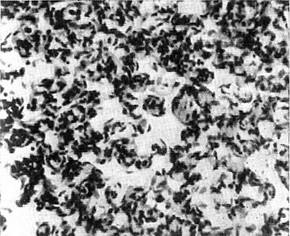

![]() Рис. 2. Злоякісна лимфангиоэндотелиома. |

Злоякісні лимфангиоэндотелиомы надзвичайно рідкісні. Можуть розвиватися в

молочних залозах через кілька років після мастектомії. Мікроскопічно характеризуються наявністю численних, позбавлених еритроцитів щілин і порожнин, вистелених великими атиповими клітинами, місцями утворюють сосочкові структури і солідні поля (рис. 2).